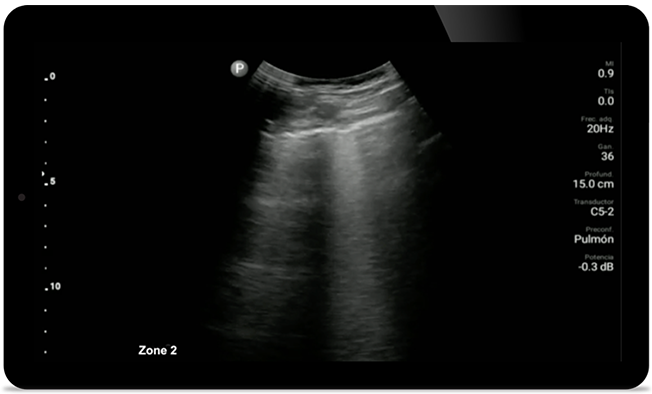

Keep an eye on COVID pneumonia

Keep an eye on COVID

pneumonia

Lumify can help give results similar to a chest CT when evaluating pneumonia and adult respiratory distress syndrome.

Padstatic case example image

See more when it counts

From revealing the subtle details of an image to uncovering enriched tissue definition from multiple angles, Lumify can help you make real-time decisions with more confidence from assessment through recovery.